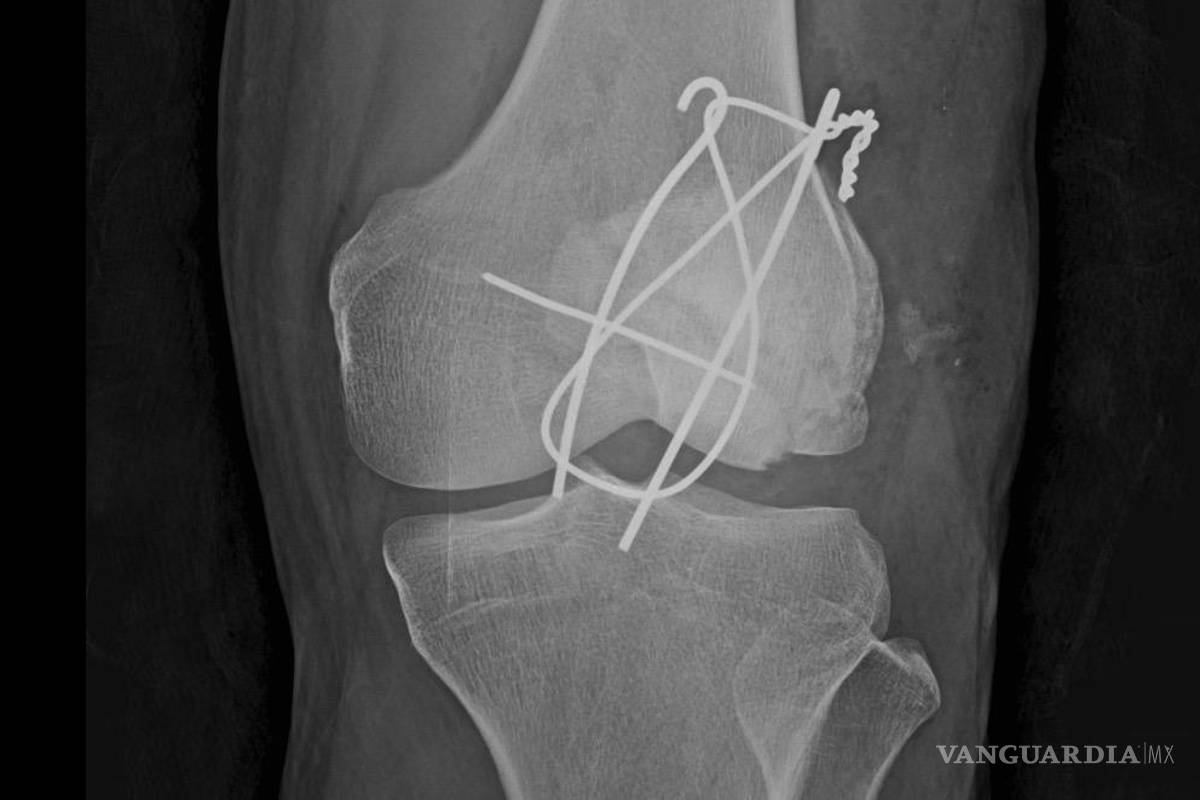

Taft afirmó que la ayuda de emergencias tardó en llegar y que, después de 50 minutos en la vía pública, fue trasladada por una ambulancia privada a la Cruz Roja, donde recibió una cirugía de emergencia. Detalló que salió del quirófano “con 3 clavos y un alambre para unir los pedazos de la rótula”, además de múltiples puntos de sutura.